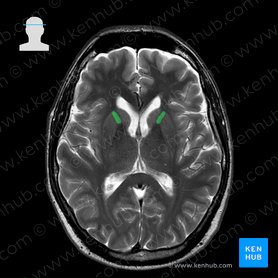

Ventricles of the brain: Anatomy and pathology | Kenhub This space is therefore occupied by a clear fluid that suspends the brain within the cranial vault. The fluid (cerebrospinal fluid) is produced in the ventricular system of the brain. There are four such hollow spaces in the brain that house cerebrospinal fluid (CSF): two lateral ventricles, a third ventricle and a fourth ventricle. Key facts. nobaproject.com › modules › the-brainThe Brain | Noba Figure 1. An MRI of the human brain delineating three major structures: the cerebral hemispheres, brain stem, and cerebellum. The brain uses oxygen and glucose, delivered via the blood. The brain is a large consumer of these metabolites, using 20% of the oxygen and calories we consume despite being only 2% of our total weight. However, as long ... Frontiers | 101 Labeled Brain Images and a Consistent Human Cortical ... Labeled anatomical subdivisions of the brain enable one to quantify and report brain imaging data within brain regions, which is routinely done for functional, diffusion, and structural magnetic resonance images (f/d/MRI) and positron emission tomography data. Brain lobes - annotated MRI | Radiology Case | Radiopaedia.org Association of Midlife Hearing Impairment With Late-Life Temporal Lobe Volume Loss. Nicole M. Armstrong et al., JAMA Otolaryngology Head Neck Surgery, 2019. Imaging Characteristics of Cerebral Autosomal Dominant Arteriopathy with Subcortical Infarcts and Leucoencephalopathy (CADASIL) Dragan Stojanov et al., BJBMS, 2015.